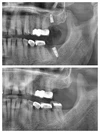

Implant tedavisi

Periimplantitis

Peri-İmplant Mukozitis